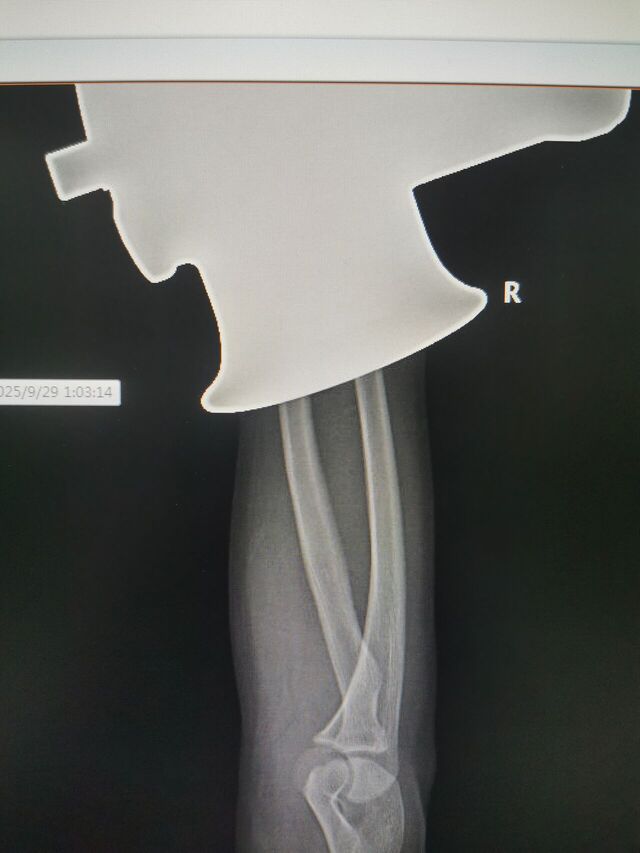

注定又是一个不眠夜!

16岁手进绞肉机了

IMG_20250923_101745.jpg

IMG_20250929_150141.jpg

IMG_20250929_150124.jpg